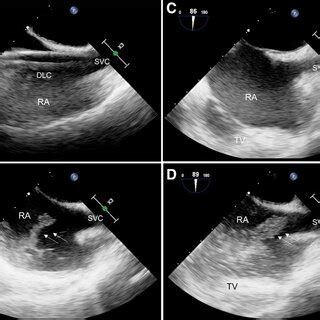

Now, let’s get into the nitty-gritty of how to get the perfect view. First, remember the patient should be lying on their left side, which is known as the left lateral decubitus position. This helps bring the heart closer to the chest wall. The probe itself is the magic wand, and the specific type you use (usually a phased array) is designed for this kind of imaging. Then comes the tricky part: the probe position. Imagine you are trying to catch the sun at the optimal angle. The goal is to position the probe under the sternum (the breastbone), aiming slightly towards the patient’s right shoulder. The idea is to align the ultrasound beam with the vena cava so you can see them clearly as they enter the right atrium. Be patient and adjust slightly until you get the best image. The orientation marker on the probe is your best friend here; it should point toward the patient’s right. It may take some practice, but you’ll get the hang of it.

Alright, let’s break down the process step-by-step for the bicaval view echo probe position . First, you’ll need the right equipment: an ultrasound machine, the right kind of probe (usually a phased array), and some acoustic gel (that stuff that makes everything glide smoothly). The patient should be positioned in the left lateral decubitus position. This positioning moves the heart closer to the chest wall, making it easier to get clear images. Now, apply the acoustic gel liberally to the probe head. This helps eliminate air pockets and ensures good contact with the skin. Place the probe just below the sternum, aiming towards the patient’s right shoulder. Gently angle the probe and try to visualize the right atrium and the vena cava. Remember to keep the probe flat against the chest wall to get the best contact and minimize any loss of image quality. Slight adjustments are often necessary to find the sweet spot, the one where the images are super clear. Scan through the various angles to see which one gives you the best picture of the superior and inferior vena cava entering the right atrium.